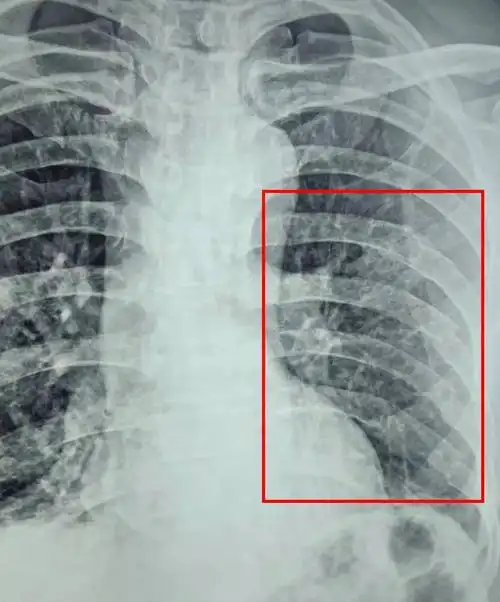

【同安精品外科7—骨折内固定术】李晓奇主任治疗肋骨骨折